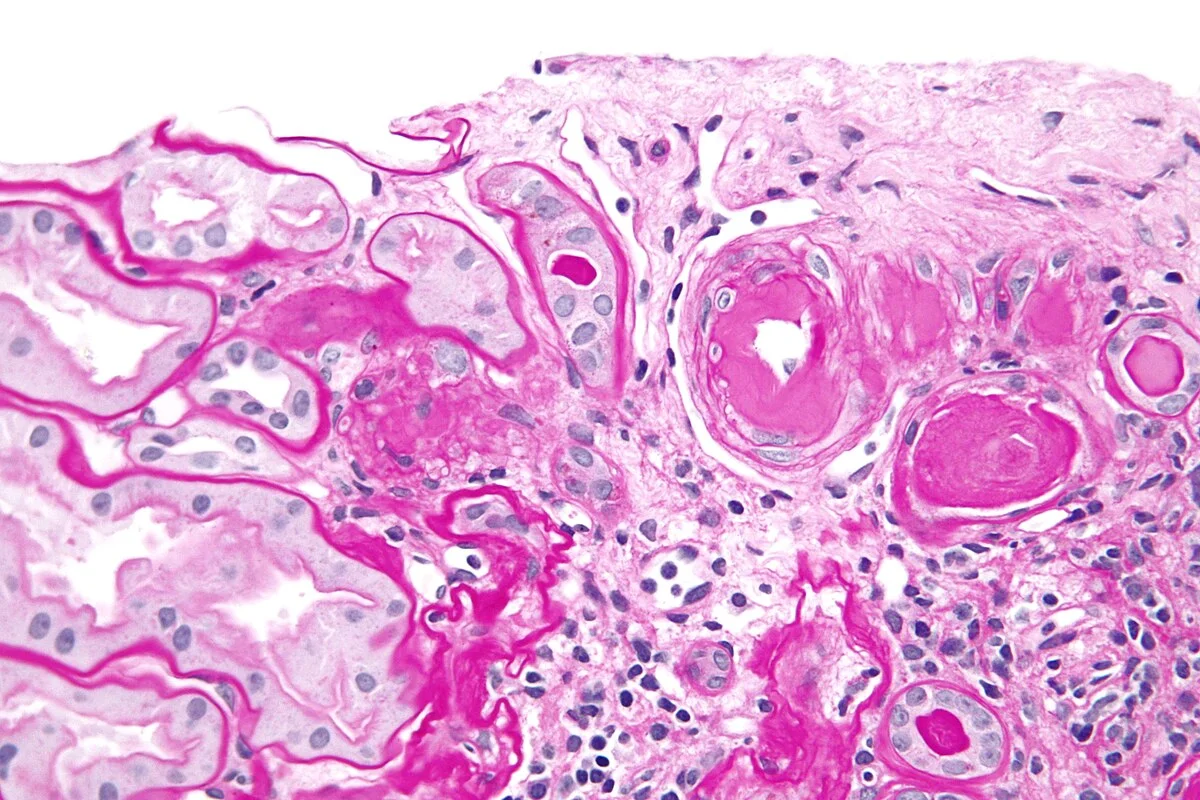

• Neoplastic proliferation phase represents the uninhibited growth of tumor cells characterized by neo-angiogenesis and restricted water diffusion on mpMRI.

• Dynamic contrast-enhanced MRI necessitates rapid temporal resolution to capture the wash-in and wash-out kinetics of contrast agents in tumor microvasculature.